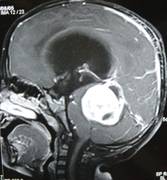

Torsion of Left Undescended Testis (Pre operative and Operative Photo)